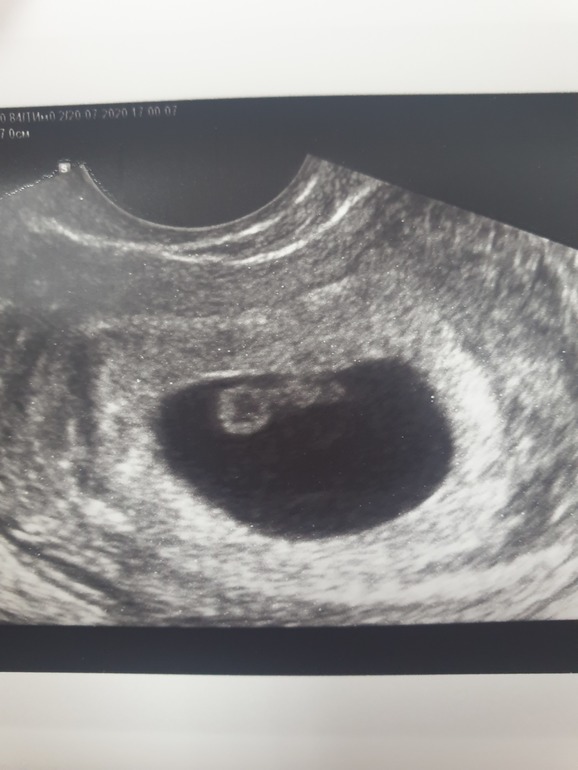

Первое узи 7 недель ❤

УЗИ, КТГ, доплерУзистка сказала все хорошо, несмотря на позднюю овуляцию (на 20 дц) она говорит, что плод на 6 недель 6 дней))

Сердечко бьется,120 ударов насчитали, все показали и дали послушать, я аж прослезилась, муж тоже сидел улыбался))

Гляньте кто разбирается, все же хорошо?)

Мой малышик❤